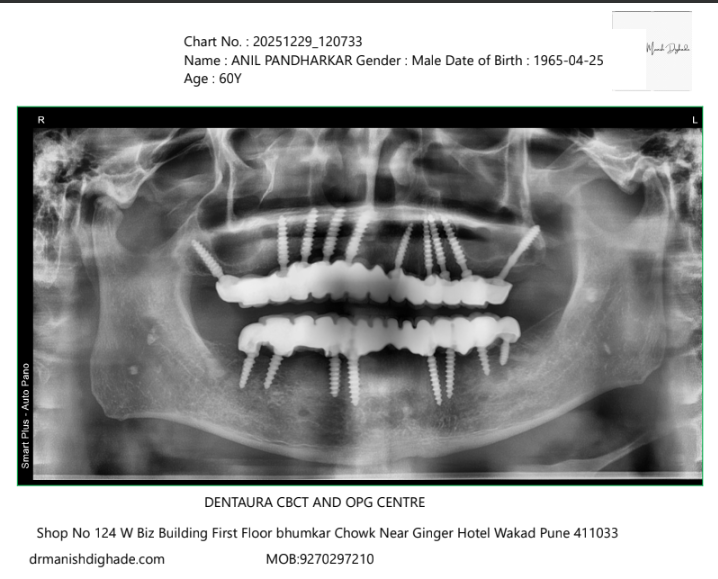

X-Ray Analysis

OPG — After

Radiographic Findings

The post-operative OPG shows successfully placed basal implants in both upper and lower jaws with proper alignment and support for fixed prosthesis. This confirms strong anchorage and immediate loading capability, enabling fixed teeth delivery within 3 days.